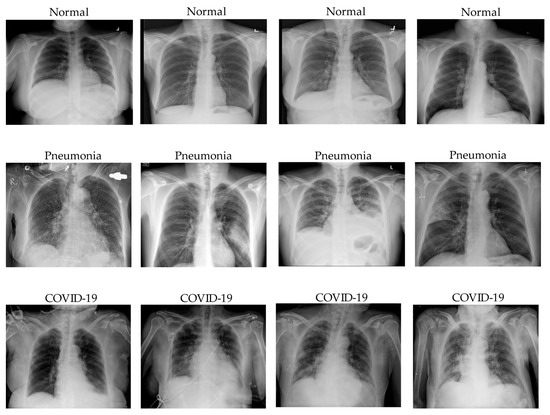

The total number of COVID-19 images is 9446, normal is 9668, and pneumonia is 9828. The Chest X-ray images were selected from Guangzhou Women and Children’s Medical Center, Guangzhou. All those images were collected as the clinical checking routine for patients suffering from pneumonia. The chest X-ray images were cleaned to make sure the quality of the input images was acceptable to feed into deep neural models. These images were classified by two expert radiologists and double-checked by a third radiologist. Three classes of chest X-ray images are illustrated in the Figure 1 with respect to normal, pneumonia, and COVID-19 cases.

Figure 1. Image samples from the customized COVID-19 classification dataset with respect to Normal, Pneumonia, and COVID-19 classes.